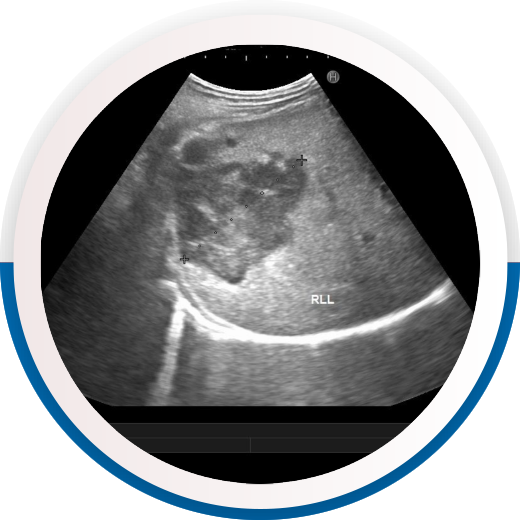

The WFUMB Interactive Case of the Month section produces consistently high visitor numbers, month on month which proves to us there is a thirst for cases, and a deep interest in continual learning amongst our audience.

Much of the success of the Case of the Month section can be attributed to the Editors of the content. Caroline Ewertsen took over the interactive case of the month in 2019, and then in 2022 Jonathan Cohen joined, both have diligently sought and checked through hundreds of cases to furnish this well-visited section.

WFUMB would like to give thanks to both Caroline and Jonathan who have dedicated so much time to keeping this section running and making it successful.

In May 2025, our two new Case Editors officially take on the job of seeking and editing new cases for WFUMB. We welcome Edda Chaves and Antonio Carlos Matteoni de Athayde, to the case team and hope they can continue the success of such a well-visited area of the WFUMB site.

For us to continue offering high quality cases we need to ask for your help. We would like to invite our member federations to submit cases for publication on the WFUMB web site and across our social media channels.

Submission is easy!

Please invite your members to use the following submission template which guides them through the information required and in what format. If language is a barrier, assure your candidates that we have a team here at WFUMB who can translate so as not to be put off! Once a case is completed and ready for submission, it simply needs to be emailed to our Case of the Month Editorial Team, Edda Chaves and Antonio Matteoni, who will assess the case ready for publication.

We would be grateful if you could circulate this call for cases amongst your members. We look forward to receiving exciting and interesting cases which everyone can enjoy!